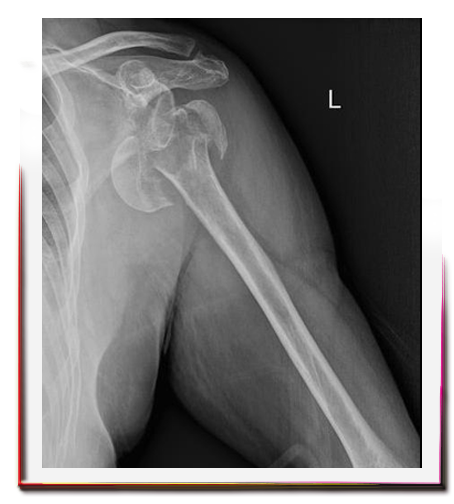

Proksimal humerus, kolun omuz eklemine yakın olan üst kısmının adıdır. Omuz kırığı denilince genellikle proksimal humerus kırıkları kastedilir. Erişkin kırıklarının %5’ ini oluşturur. Genellikle 60 yaş üzerinde, kemik mineral yoğunluğu düşük hastalarda basit düşmeler sonrasında görülür.

Omuz üzerine düşme yada el üzerine düşme sonrasında başlayan şiddetli omuz ağrıları, hareket ettirememe durumu omuz çevresinde kırık olabileceğini düşündürmelidir.